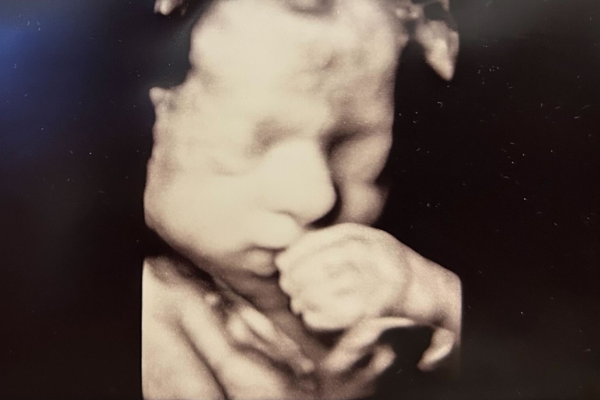

Har du ikke allerede booket en 3D/4D scanning, bør du gøre det. Og det ville vi også skrive, selvom vi ikke solgte det selv. Det er bare en fantastisk oplevelse!